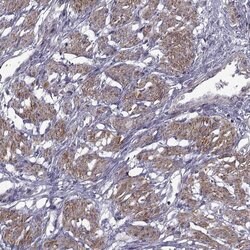

| Immunohistochemistry (Paraffin), Immunocytochemistry | |